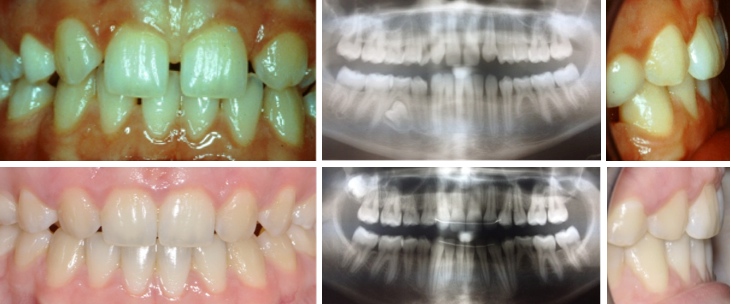

Fall 3: Aufgewanderte Zahnreihe

Therapie: Spezialapparatur zum zurückschieben der Zähne und Gartenhag nur im Oberkiefer notwendig